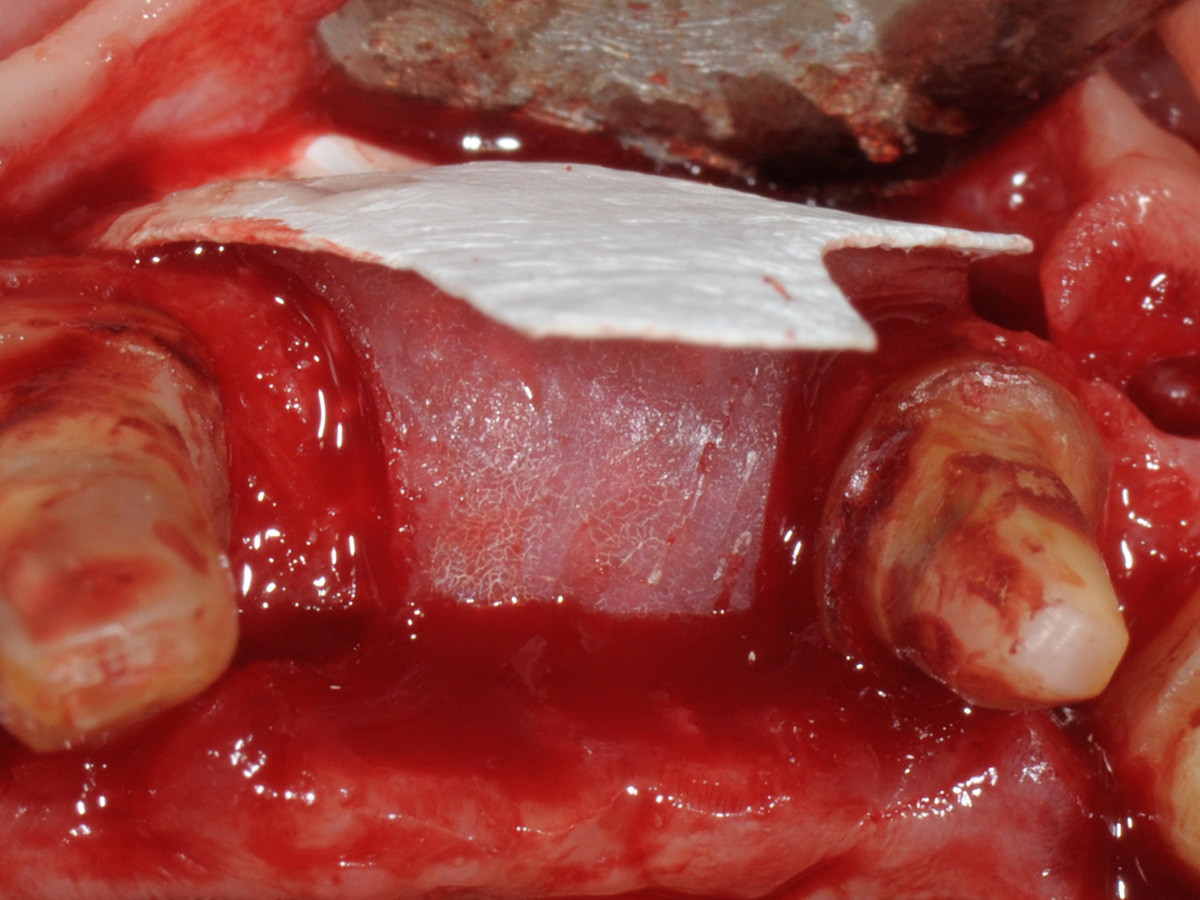

Abbildung 7

Abbildung 8

Aufbau mit OsteoBiol® mp3, Bone Lamina Soft und Evolution.